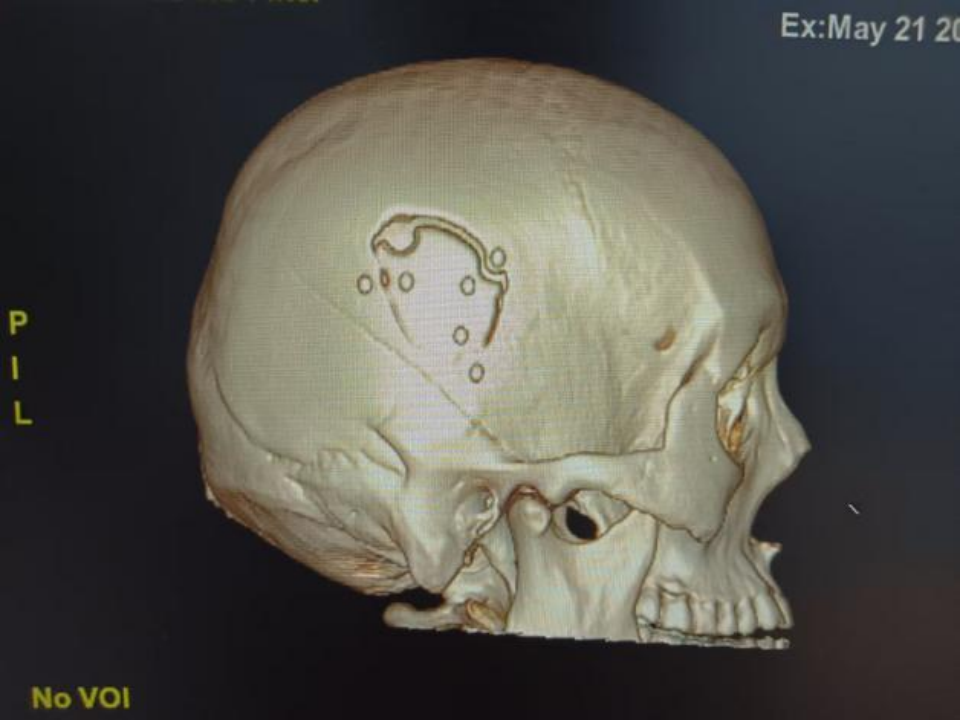

△术后颅脑CT

△术后颅脑CT三维重建